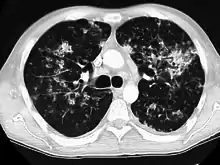

CT image showing diffuse GGOs throughout both lungs. An abscess is also noted in the right lung (screen left). - Adenocarcinoma in situ of the lung